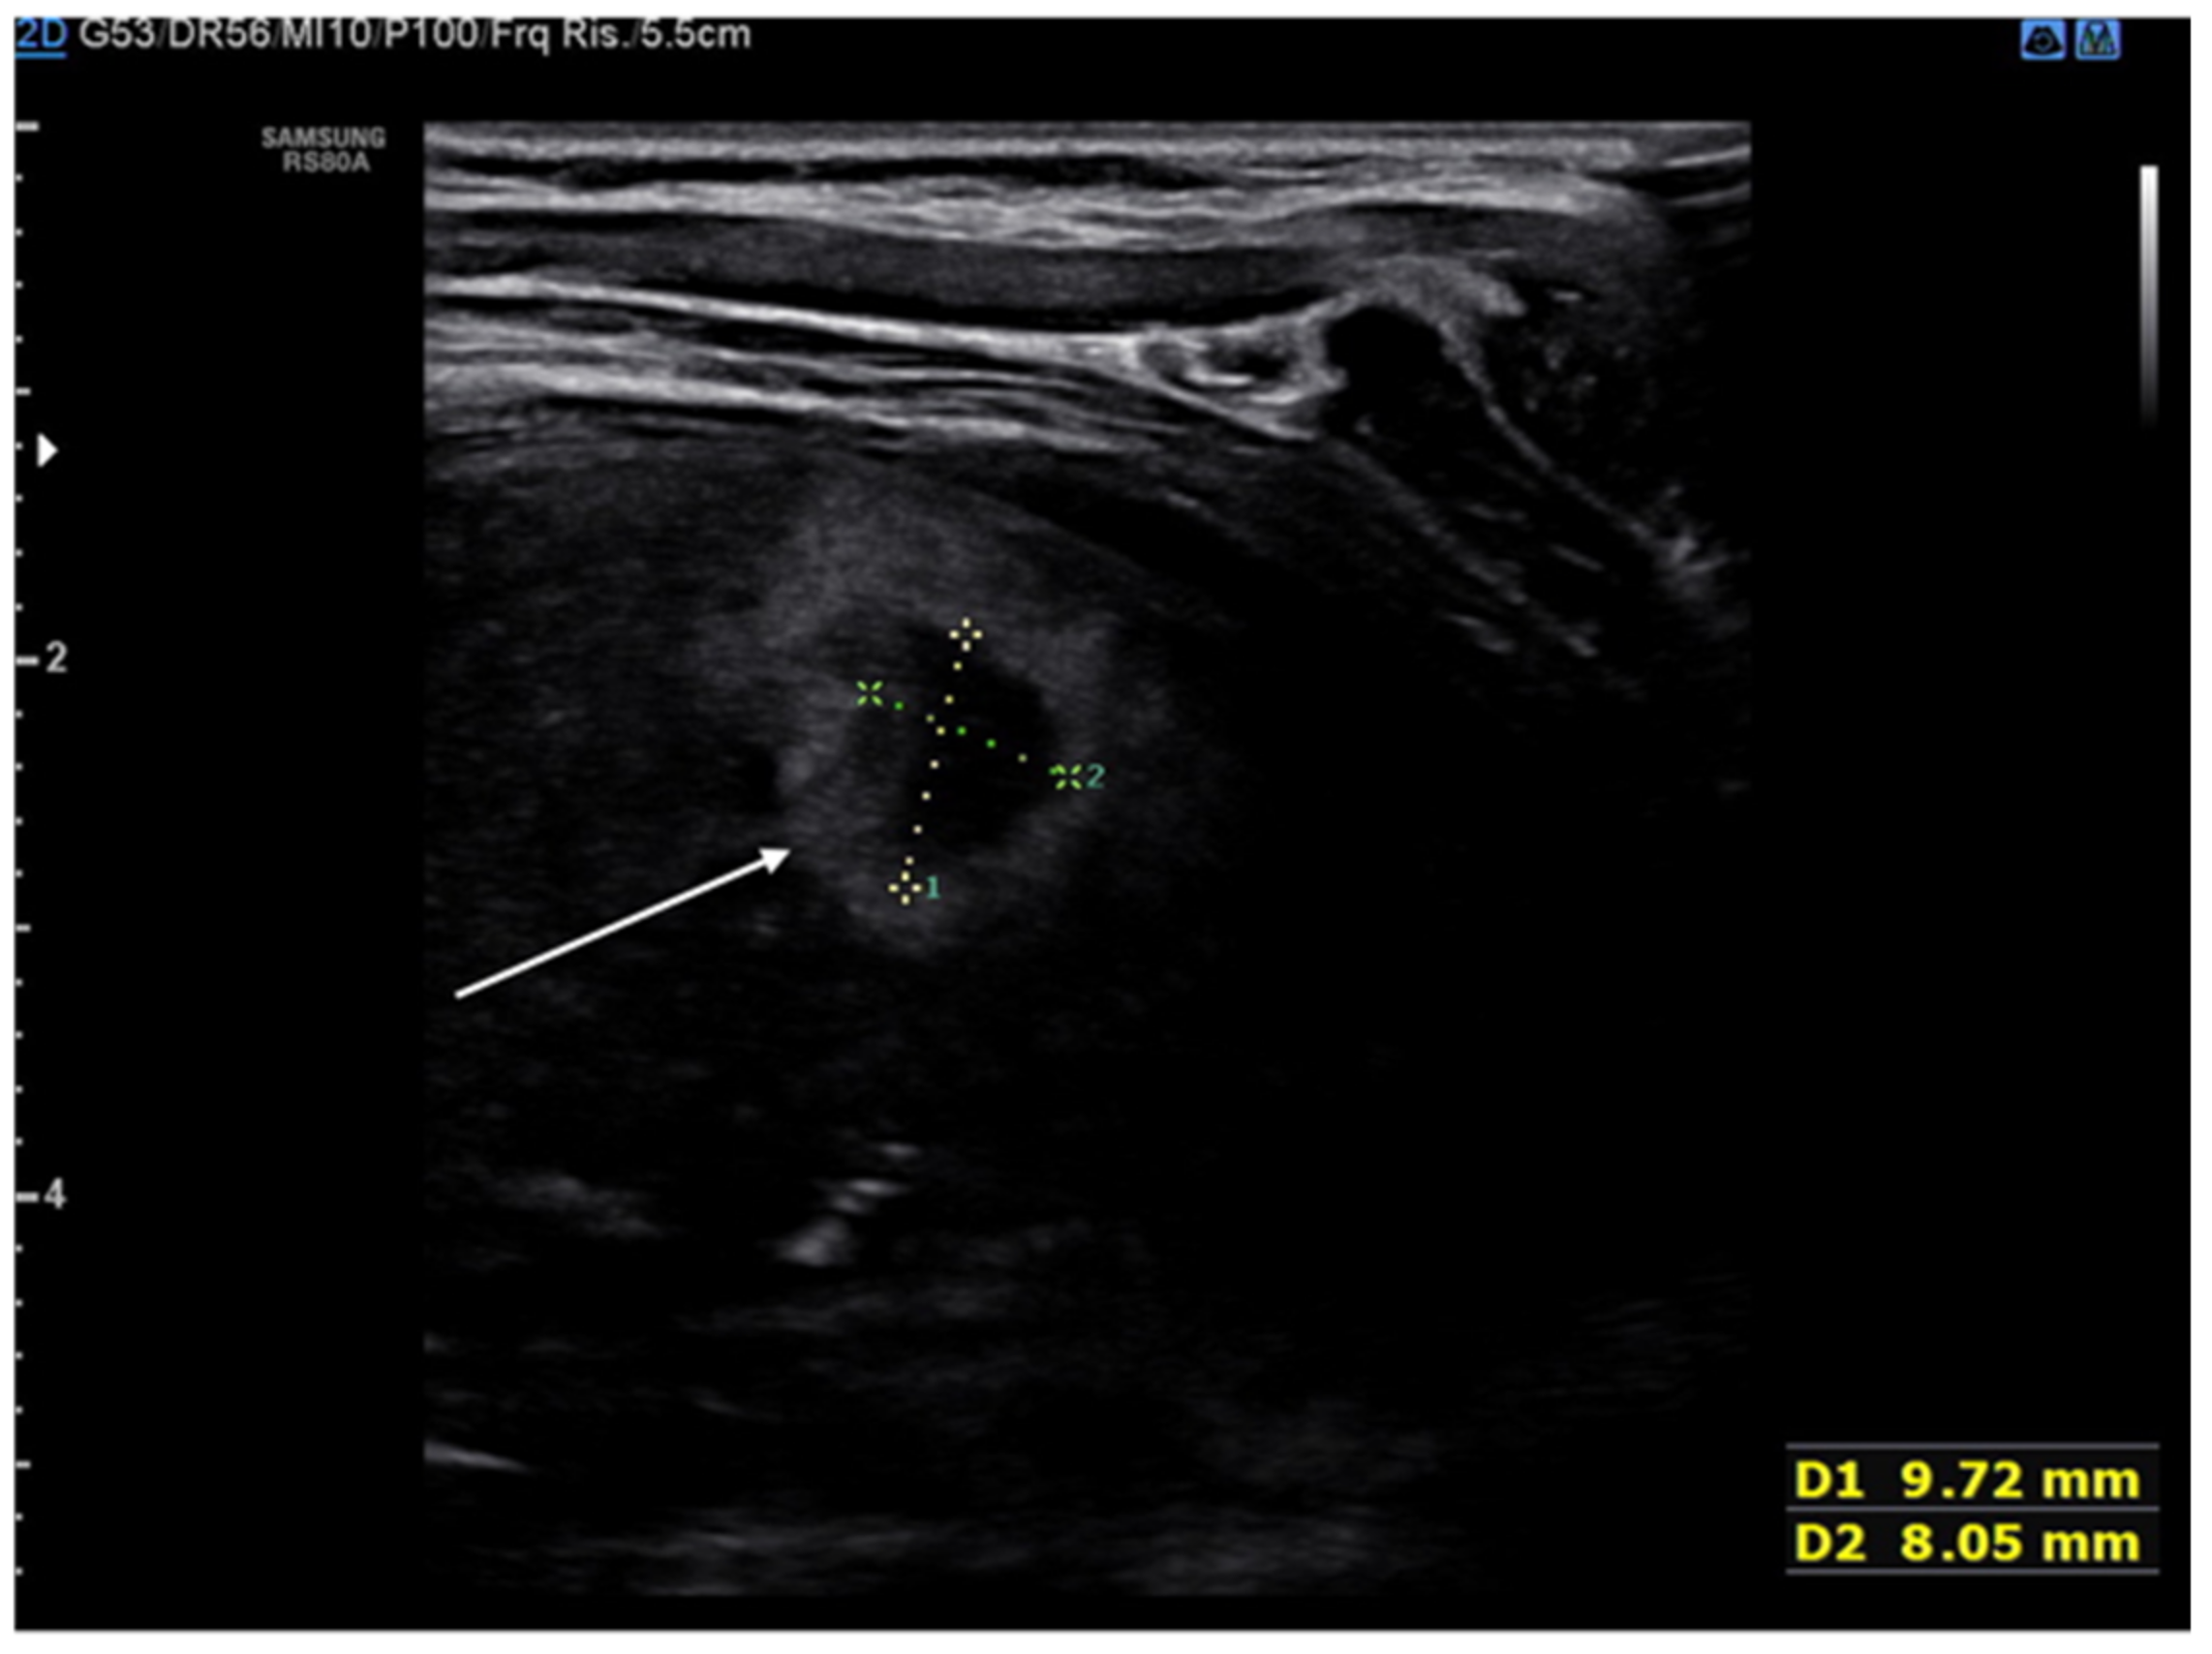

8. Pneumothorax, Pleural Effusion Empyema and Lung Abscess

- Kraft, C.; Lasure, B.; Sharon, M.; Patel, P.; Minardi, J. Pediatric Lung Abscess Immediate Diagnosis by Point-of-Care Ultrasound. Pediatr. Emerg. Care 2018, 34, 447–449. [Google Scholar] [CrossRef]

- Lin, F.; Chou, C.; Chang, S. Differentiating pyopneumothorax and peripheral lung abscess: Chest ultrasonography. Am. J. Med. Sci. 2004, 327, 330–335. [Google Scholar] [CrossRef]

- Chen, H.J.; Yu, Y.H.; Tu, C.Y.; Chen, C.H.; Hsia, T.C.; Tsai, K.D.; Shih, C.M.; Hsu, W.H. Ultrasound in peripheral pulmonary air-fluid lesions. Color doppler imaging as an aid in differentiating empyema and abscess. Chest 2009, 135, 1426–1432. [Google Scholar] [CrossRef] [PubMed] [Green Version]

- De Benedictis, F.; Kerem, E.; Chang, A.B.; Colin, A.A.; Zar, H.J.; Bush, A. Complicated pneumonia in children. Lancet 2020, 396, 786–798. [Google Scholar] [CrossRef]